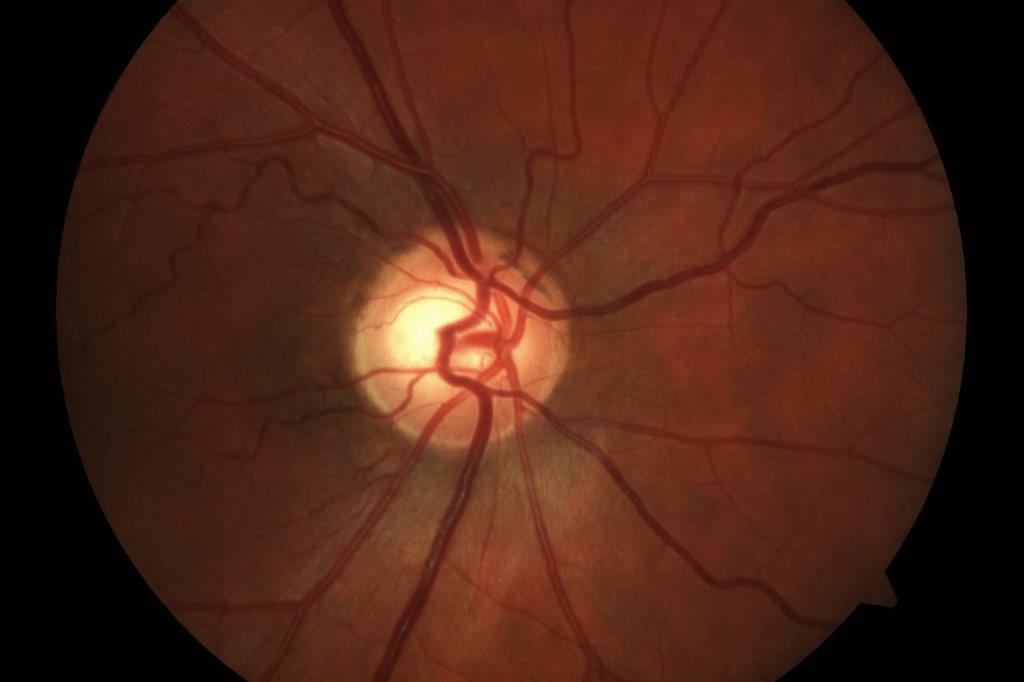

A wāhine Māori presented to the acutes clinic with type-1 uncontrolled diabetes and a painful, red left eye. Clinical examination revealed a steamy cornea with 360° neovascularisation of the iris and angle and IOP of 62mmHg. Visual acuity was 6/12 in the right eye and perception of light in the affected left eye. She had bilateral cataracts and fundus examination showed bilateral proliferative diabetic retinopathy (although the view was hazy in the left eye due to the steamy cornea). Treatment was intravenous acetazolamide, which instantaneously reduced IOP to 48mmHg. Left eye intravitreal Avastin (bevacizumab) was administered with paracentesis and IOP-lowering drops. A review after three days showed a hyphaema and an IOP of 42mmHg on maximal medication, including oral acetazolamide. Fundus examination showed advanced optic disc damage with a disc damage likelihood scale (DDLS) 8 in the left eye and moderate disc damage, DDLS 6, in the right eye. She underwent bilateral pan-retinal photocoagulation for proliferative diabetic retinopathy.